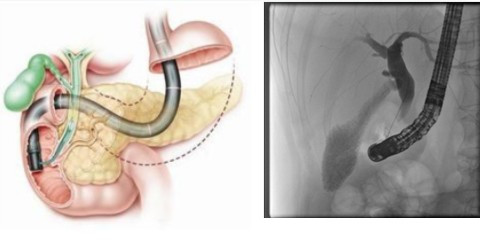

所謂ERCP技術(shù),是指經(jīng)內(nèi)鏡逆行性胰膽管造影術(shù)(ERCP)是指將十二指腸鏡插至十二指腸降部,找到十二指腸乳頭,由活檢管道內(nèi)插入造影導(dǎo)管至乳頭開口部,注入造影劑后x線攝片,以顯示胰膽管的介入技術(shù)。

ERCP(消化介入)示意圖。注:右側(cè)圖像采集自消化介入金標(biāo)準(zhǔn)移動(dòng)C形臂——Alien -E